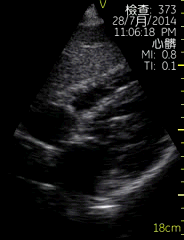

胸骨旁左室长轴切面

| 图像名称: | 胸骨旁左室长轴切面(二维) |

| 胸骨旁左室长轴切面(二维) | | 介绍重点: | 长轴切面心肌收缩有力、二尖瓣前后叶呈镜向运动 |

| 室间隔回声中断,可见明显缺口,左室增大 |

| 左房、左室增大,室壁运动幅度降低;二尖瓣启闭受限; | | 临床用途: | 评估房室大小,心脏功能;(正常图像) |

| 室间隔缺损; |

| 左室收缩功能降低 |